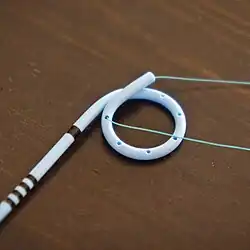

A ureteral stent (pronounced you-REE-ter-ul), or ureteric stent, is a thin tube inserted into the ureter to prevent or treat obstruction of the urine flow from the kidney. The length of the stents used in adult patients varies between 24 and 30 cm. Additionally, stents come in differing diameters or gauges, to fit different size ureters. The stent is usually inserted with the aid of a cystoscope. One or both ends of the stent may be coiled to prevent it from moving out of place; this is called a JJ stent, double J stent or pig-tail stent.

A ureteric stent may also be retrieved without the use of a cystoscope by means of a magnetic removal system. The stent inserted has a small rare earth magnet attached to its bladder end which dangles freely within the bladder. When the stent needs to be removed a small catheter with a similar magnet is inserted into the bladder and the two magnets connect and the catheter and stent can be simply removed. This eliminates the need for a costly and invasive cystoscopy in both adults and children.

Peer reviewed papers show that more than 98% of stents can be retrieved with a magnet in adults, paediatric and kidney transplant patients. Avoidance of a general anesthetic in children is very significant and also results in enormous cost-savings because the procedure no longer need to be done in the operating room.

Magnetic retrieval of the stent does not require a urologist and can be done by primary care physicians, nurse practitioners and nurses.